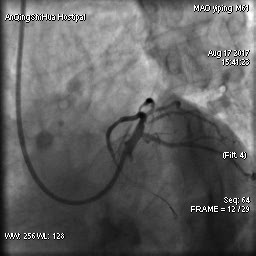

由于毛先生的病變涉及主干分叉,即復雜的真性分叉病變,為保證分支開口得到良好的開放,術(shù)者采取了操作復雜的雙支架術(shù)式,先后運用掏支架網(wǎng)眼、球囊擴張、雙球囊對吻擴張、POT技術(shù)等,實現(xiàn)了完全血運重建。術(shù)后,毛先生的嚴重心絞痛終得緩解。

術(shù)后 心臟左主干末端狹窄解除,血流通暢